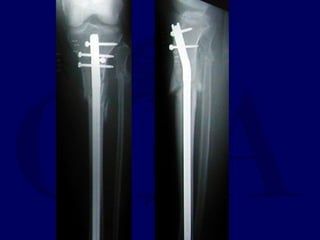

Expanded Indications • Proximal1/3 • Distal 1/3 • Increased Problems

• 53.

• Proximal Fractruesare technically more challenging • Prone to Valgus & • Pro-curvatum deformities

Technique • Screws placedon concave side of deformity.

• 56.

Blocking (Poller) Screws •Functionally narrow im canal • Increase strength and rigidity of fixation

The Use ofPoller Screws as Blocking Screws in Stabilising Tibial Fractures Treated with Small Diameter Nails • 21 patients • All healed within 3-12 months • Mean alignment 1 degree valgus, antecurvatum 2 degrees. Krettek C, et al. JBJS 81B: 963, 1999

• 58.

• Entry Sitefor Proximal fractures Critical • Reference is Lateral Tibial Spine

Proximal and DistalCases Courtesy of R. Winquist M.D. Seattle, Wa.